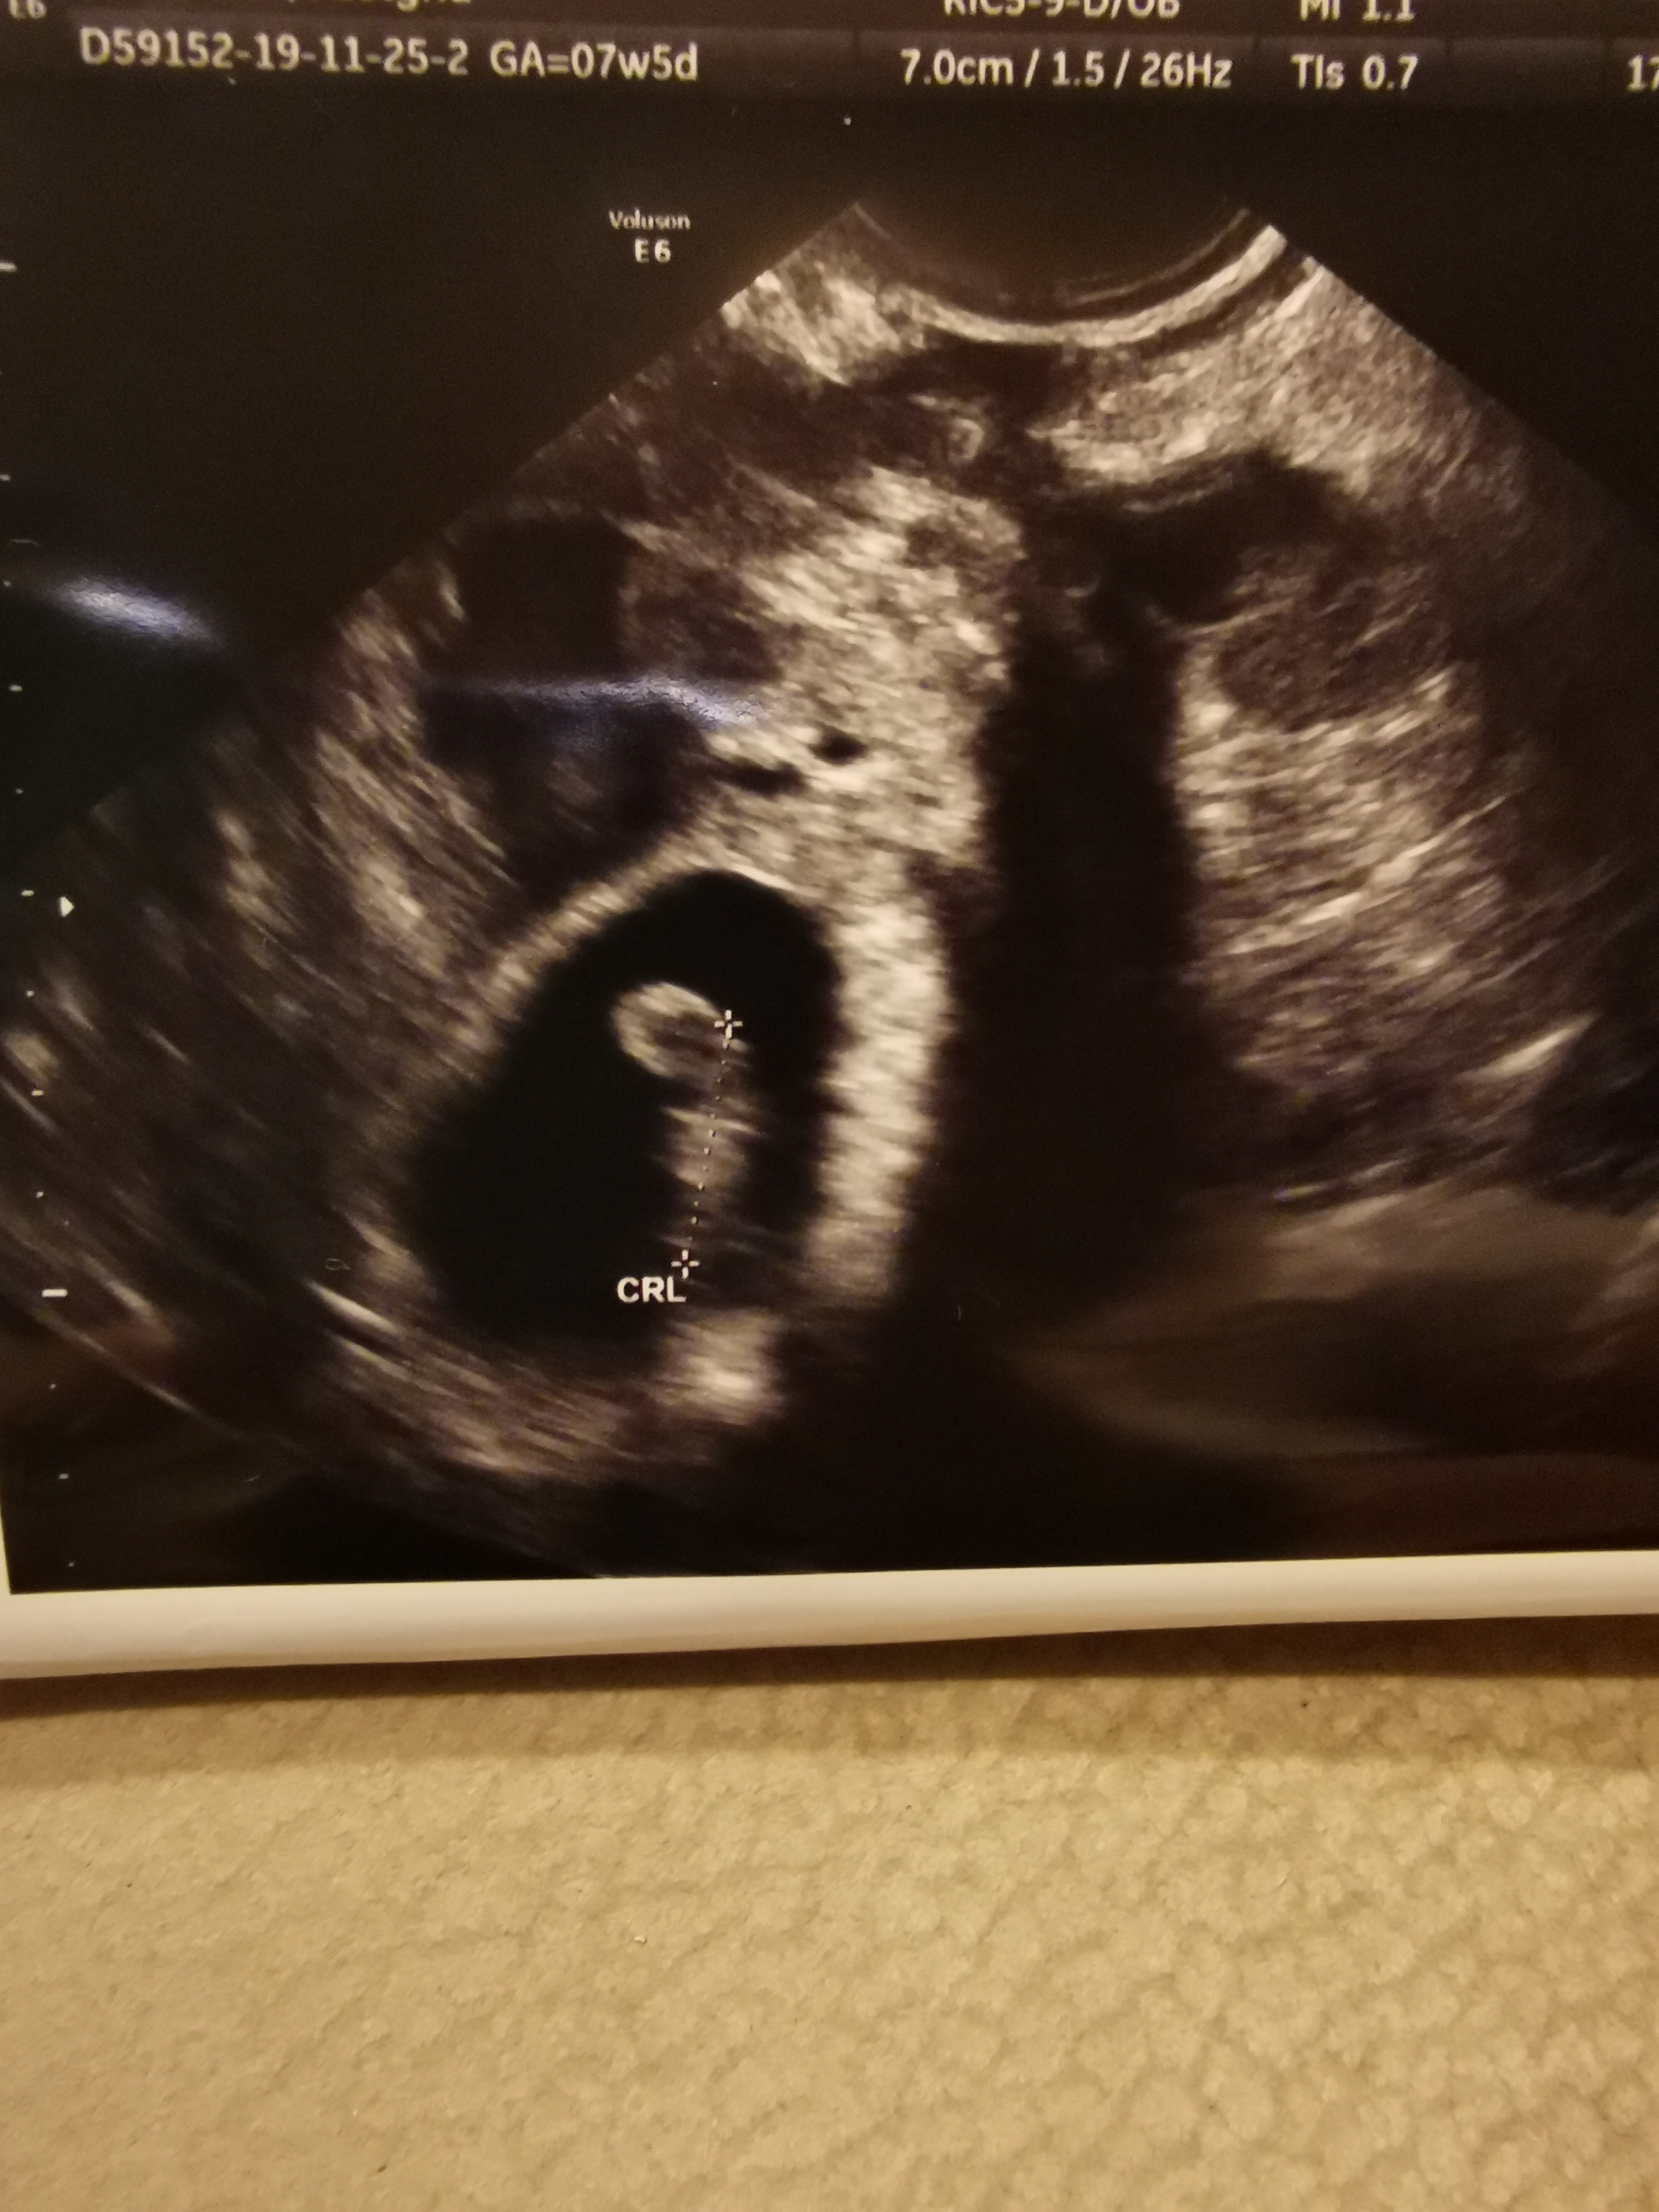

Cudne wieści [emoji6]Dziewczynki moje kochane wszystko ok [emoji3] serduszko bije jak oszalał, termin porodu 2 sierpień [emoji3] wg USG ciąża młodsza o 3 dni. Mam też krwiaka, ale mam się nim nie przejmować, mogę plamić, ale ginek dał więcej progesteronu do łykania. Kolejna wizyta 08.01 no i mam umawiać się już na prenatalne [emoji3]